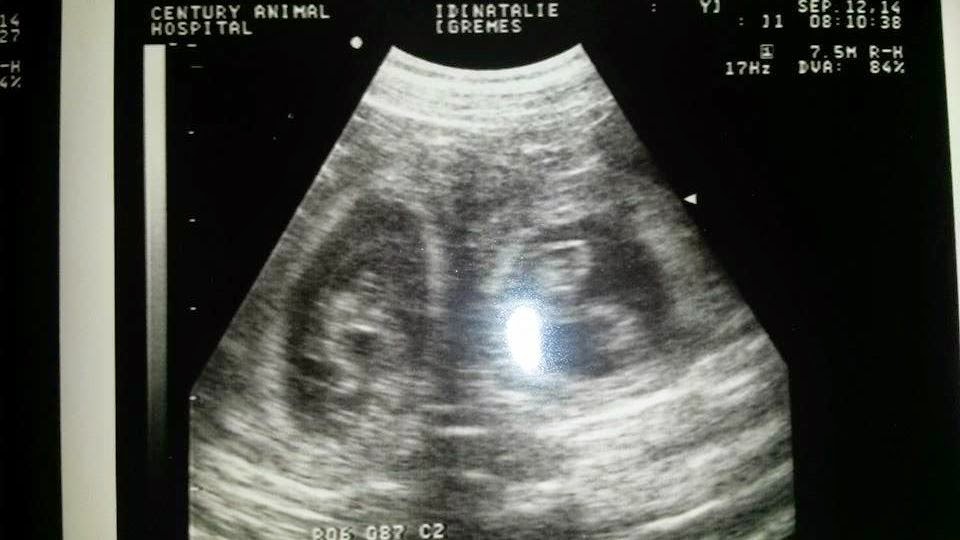

In this view you can see two of the puppies! Ultrasound does not tell you how many but only confirms pregnancy. Natalie will go back for a pre-natal check-up in a couple of weeks, and then about a week before she is due we will have an x-ray which will give us a better idea of how many puppies there are.